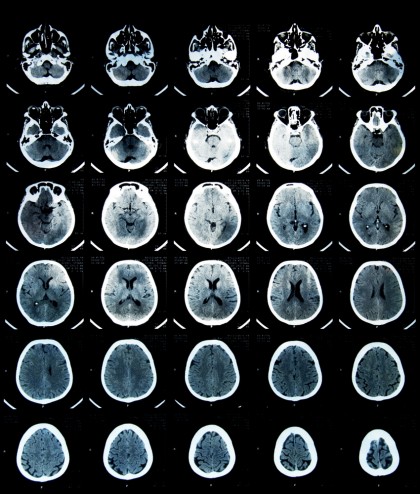

Studiul publicat în Journal of the American Academy of Child & Adolescent Psychiatry a fost realizat în cadrul Generation R Study, un studiu de cohortă desfășurat în Rotterdam, Olanda, care a urmarit 9.503 copii născuÈ›i între 2002 È™i 2006. Dintre aceÈ™tia, 3.328 au fost invitaÈ›i la o evaluare imagistică cerebrală cu rezonanță magnetică (MRI) între 9 È™i 12 ani, iar 2.229 de participanÈ›i au avut date valide pentru analiza efectului temperaturii ambientale asupra conectivității funcÈ›ionale cerebrale.

Temperatura ambientală a fost estimată cu ajutorul modelului UrbClim, care oferă valori la rezoluÈ›ii de 100m, fiind validate cu date meteorologice locale. Pentru fiecare participant, s-a calculat temperatura medie zilnică pe parcursul a 7 zile anterioare evaluării MRI. Scanările cerebrale au fost realizate cu un aparat 3.0T Discovery MR750W, iar datele au fost prelucrate utilizând algoritmul fMRIPrep pentru analiza conectivității funcÈ›ionale în 13 reÈ›ele neuronale de repaus, inclusiv hipocampul È™i amigdala.